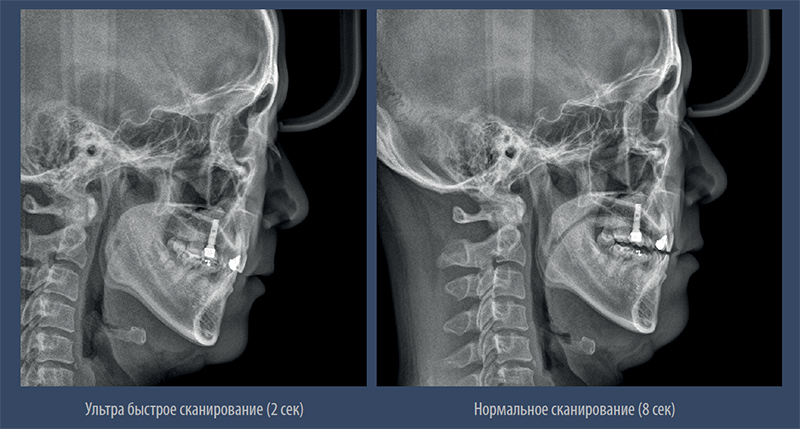

Режим быстрого сканирования

PAPAYA 3D позволяет добиться качественного результата с минимальной дохой облучения в режиме быстрого сканирования длительностью 7,7 сек.

Режим быстрого сканирования.

– Минимальная доза облучения в режиме быстрого сканирования

– Качественное изображение без артефактов движения и искажений

Цефалометрия

Высокое разрешение съёмки ТРГ

– Быстрый режим позволяет получить качественное цефалометрическое изображение без артефактов движения и искажений